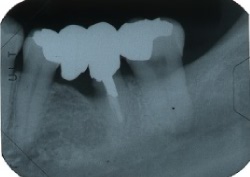

●骨が失われている所は、レントゲンを撮ると黒い影になって写ります。

●エムドゲイン塗布後、徐々に影が、うすくなってきています。

●影が無くなり、骨ができています。